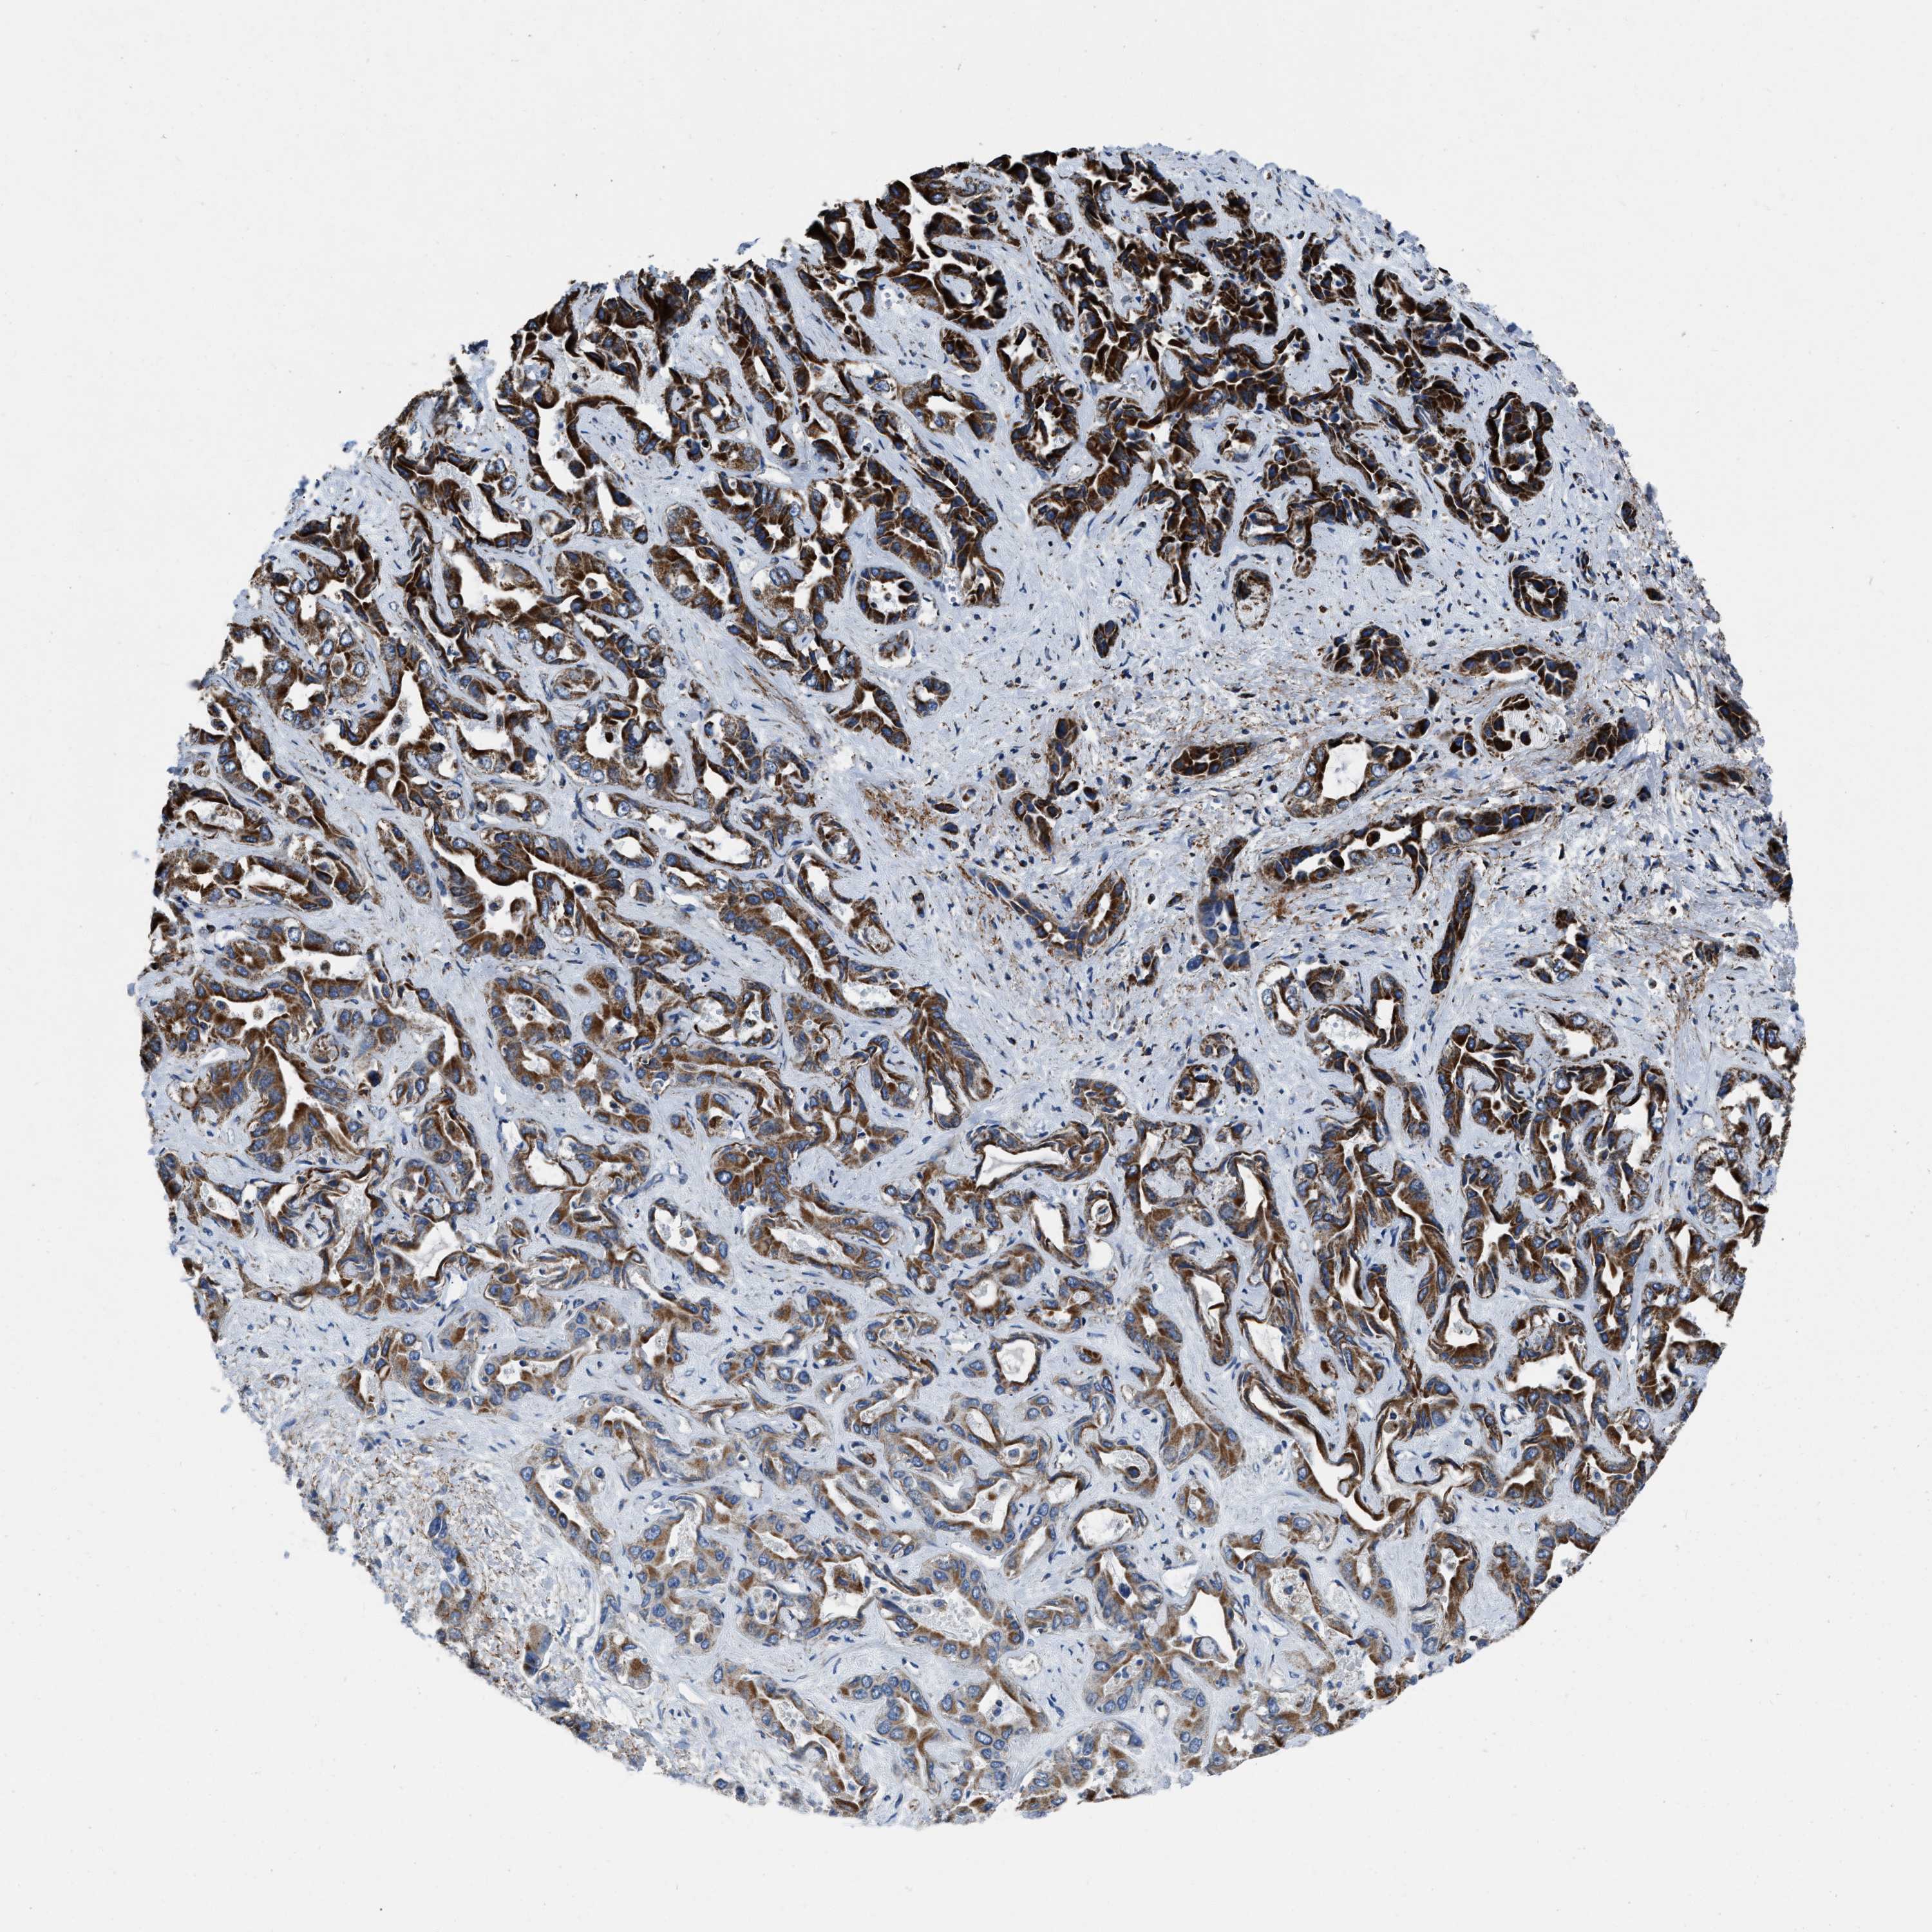

LIVER CANCER - Protein expressioni

A mouse-over function shows sample information and annotation data. Click on an image to view it in a full screen mode. Samples can be filtered based on level of antibody staining by selecting one or several of the following categories: high, medium, low and not detected. The assay and annotation is described here.

Note that samples used for immunohistochemistry by the Human Protein Atlas do not correspond to samples in the TCGA dataset.

Antibody stainingi

Antibody staining in the annotated cell types in the current human tissue is reported as not detected, low, medium, or high, based on conventional immunohistochemistry profiling in selected tissues. This score is based on the combination of the staining intensity and fraction of stained cells.

Each image is clickable and will lead to virtual microscopy that enables deeper exploration of all samples and also displays staining intensity scores, fraction scores and subcellular localization as well as patient and tissue information for each sample.

Antibody HPA018893

Staining

High

Medium

Low

Not detected

Intensity

Strong

Moderate

Weak

Negative

Quantity

>75%

75%-25%

<25%

None

Location

Nuclear

Cytoplasmic/membranous

Cytoplasmic/membranous,nuclear

Cholangiocarcinoma

Carcinoma, Hepatocellular, NOS